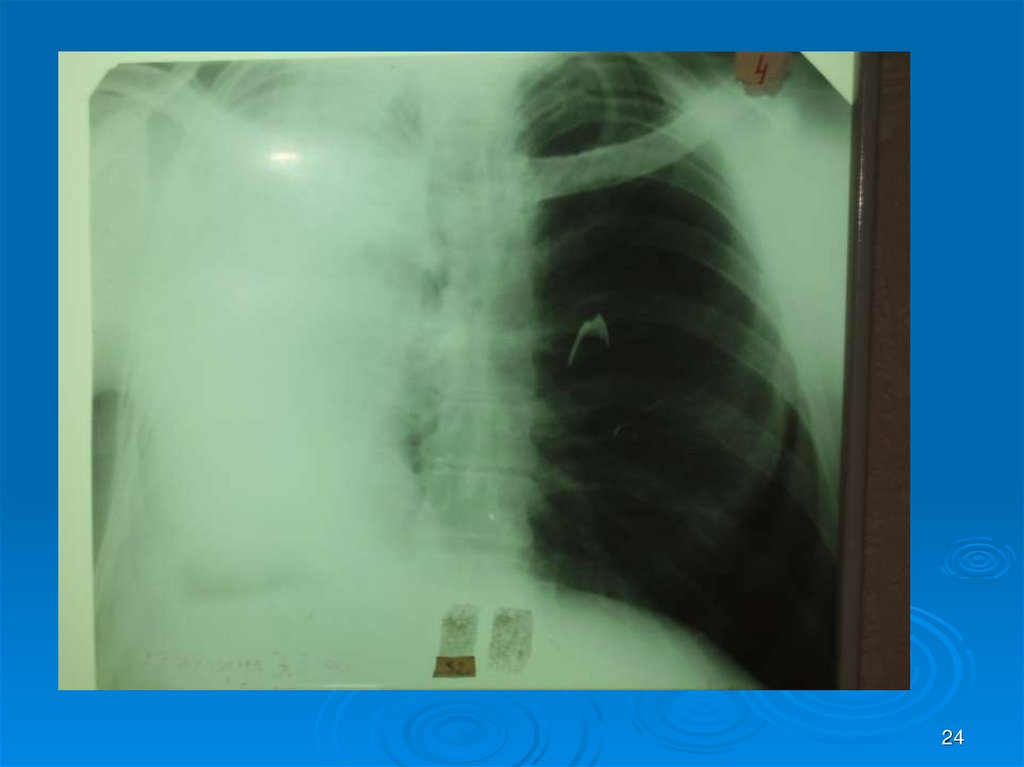

24.

24